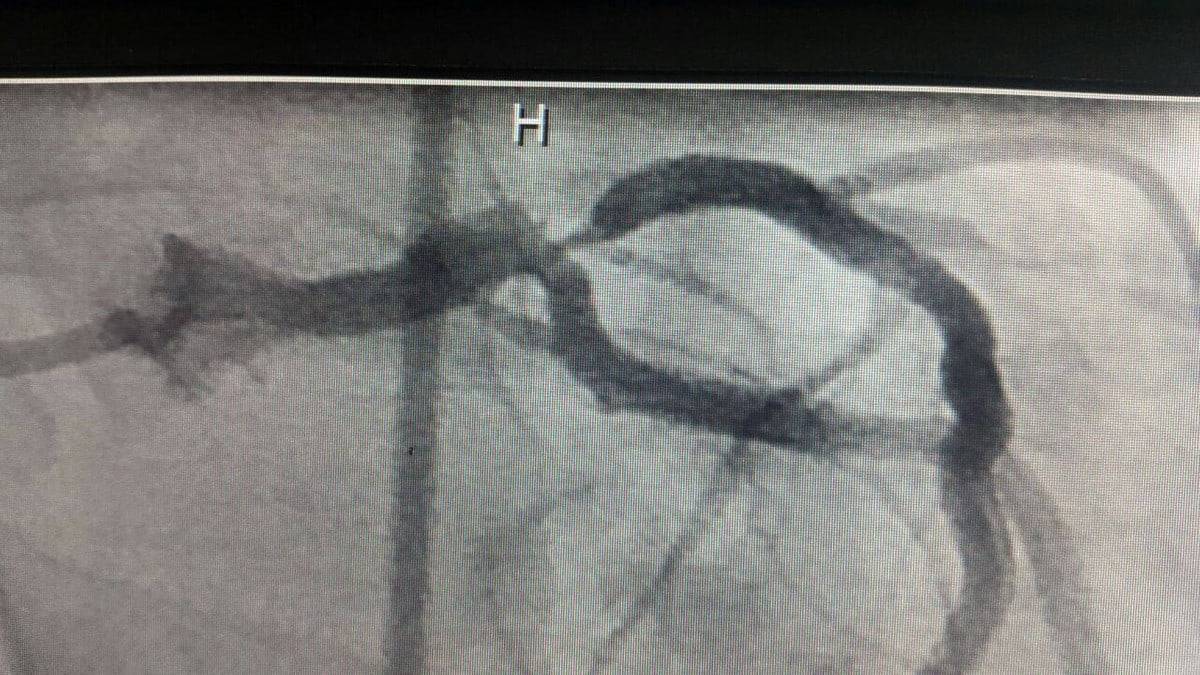

آنژیوگرافی سی-تی Computed tomography angiography یا CTA، روشي است كه با استفاده از اشعه X ، جريان خون در شريانها، سياهرگها مشاهده مي‌شود.

در مقايسه با كتتر آنژيوگرافي، كه متضمن قرار گرفتن كتتر و تزريق ماده كنتراست (حاجب)  به درون شريانها و سياهرگهاي بزرگ بود، CTA كمتر تهاجمي و پروسه راحتري براي بيمار است. ماده كنتراست (حاجب) توسط سوزن يا كتتر كوچك به داخل سياهرگهاي محيطي كوچك تزريق مي‌شود. در اين روش بسياري از بيماران نياز به بستري شدن در بيمارستان را ندارند.

CTA براي تشخيص و گرفتگي شريانهاي كاروتيد كه خون را از قلب به مغز مي‌رساند، به‌كار مي‌رود. زماني كه يك stent درجريان رگهاي  بيمار شده قرار گيرد، با كمك angiography  CT  مشخص مي‌‌شود كه به منظور اصلي رسيده‌ايم يا خير. بررسي شريانهاي مغزي مي‌تواند به پزشك در تشخيص درست بيماري كمك كند.در بيماران داراي تومور، مي‌تواند به جراح در فهميدن جزئيات رگهاي تغذيه كننده تومور كمك كند.

قابليت انجام عمليات CT-Angiography  : با توجه به اينكه در چرخش تيوب (مولداشعه X )از هيچگونه تسمه و موتور گرداننده استفاده نشده و چرخش بخش چرخنده شامل تيوب و دتكتور‌ها و موارد وابسته تحت يك ميدان مغناطيسي انجام مي‌شود، سرعت چرخش تيوب همراه با تعداد رديف‌هاي زياد دتكتورها، سرعت تصوير برداري را بسيار بالا برده تا جايي كه پس از پايين آوردن و تثبيت ضربان قلب بيمار فقط با تزريق داخل وريدي ماده حاجب و با ميزان دوز دريافتي بسيار كم، نسبت به ديگر دستگاه‌ها مي‌توان تصاويري با دقت و ظرافت بسيار قابل توجه با قطاعي كمتر از 0.4mm در هر اسلايس از عروق كرونر بيماران قلبي دريافت نمود. لازم به توضيح است كه سي تي آنژيوگرافي تنها محدود به عروق كرونر نيست بلكه بررسي عروق مغزي، ريوي، سر و گردن، شريان‌هاي كليوي، شريان‌هاي اندامي و… به راحتي با دقت بالا توسط اين دستگاه انجام مي‌شود.

جالب اينجاست دقت و كيفيت تصاوير در حدي است كه در بيش از 98% موارد گزارش آنژيوگرافي آن را تاييد و تصديق مي‌كند، در واقع با اين توانايي در بيش از 95% موارد كه عدم وجود مشكل گزارش مي‌شود نياز به انجام آنژيوگرافي ضروري به‌نظر نمي‌رسد، چرا كه انجام آنژيوگرافي در CATH LAB مستلزم بيهوشي و Catheterization بوده كه استرس و احساس ريسك فراوان براي بيمار به همراه داشته لذا بيماران نيز ترجيح مي‌دهند قبل از استفاده از اين روش توسط سي تي آنژيو چك شوند و درصورت برخورد با موارد مشكوك يا نياز به آنژيوپلاستي تن به آنژيوگرافي و ريسكهاي آن بدهند،

تصاوير دريافت شده از عروق كرونر در اين روش از كيفيت خارق‌العاده اي برخوردار بوده از طرفي امكانات تعبيه شده نرم افزاري و سخت افزاري لازم جهت پزشكان، انجام كليه بازسازي‌هاي مورد نياز داخلي و حتي فضايي عروق را در اسرع وقت برايشان فراهم  و قابل ارزيابي دقيق كرده است كه از آن جمله مي‌توان تشخيص و بررسي دقيق وجود يا عدم وجود پلاكهاي كلسيم و موقعيت آنها در مسير شريانهاي كرونري قلب و نيز ديگر عوامل تنگي عروق كرونري را نام برد.